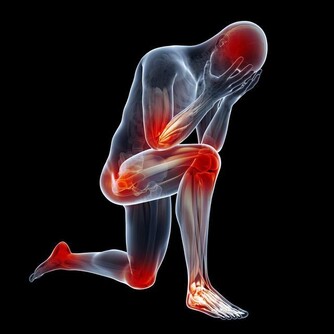

6、高血脂可以預防嗎?

高血脂可以透過生活型態如健康飲食、運動、戒菸等預防或延後發生。雖然有部份高血脂症是家族遺傳,無法預防,但仍需維持健康飲食及運動習慣,避免高血脂症可能提早報到。